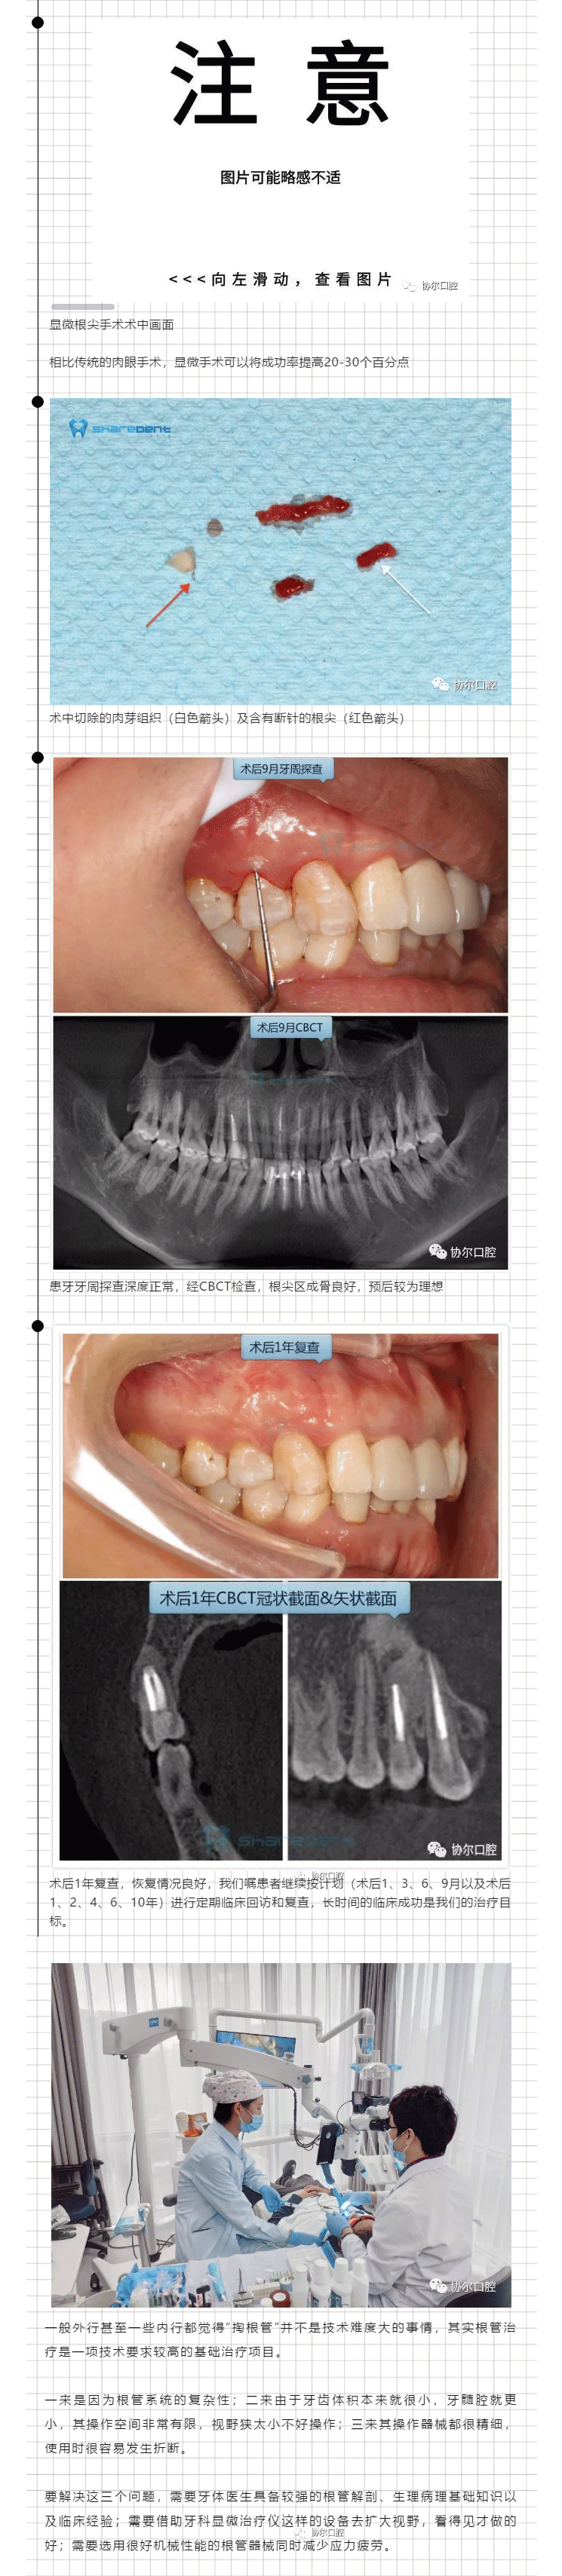

牙体牙髓

协尔周秀‖见微知著话“根管”